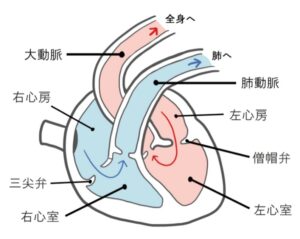

犬の心臓病の中で特に多いのが僧帽弁閉鎖不全症です。僧帽弁は左心房と左心室の間にあり、血液の逆流を防ぐ大切な弁です。

この弁がうまく閉じなくなると血液が逆流し、心臓に負担がかかります。進行すると肺に水が溜まる「肺水腫」を引き起こします。

肺水腫は心臓病の末期に表れ、肺に水が溜まった重篤な状態です。呼吸が苦しくなり、命を落とすこともある緊急性の高い病気です。レントゲン画像で確認すると、白い靄(もや)がかかって見えます。